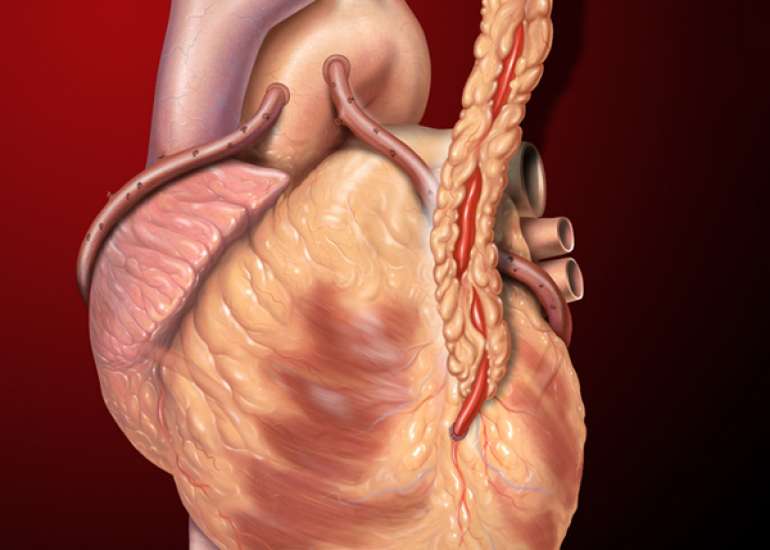

Dr. Yadava completed his medical graduation and Masters in Surgery from Maulana Azad Medical College and had joined Armed Forces as a Surgical Specialist. He cleared his DNB Examination in General Surgery in the year 1983 and completed his training in cardiothoracic surgery at the Cardio Thoracic Center, Armed Forces Medical College, Pune in 1985. For advanced training, went to Australia and worked under and along with some of the greatest cardiac surgeons of recent times. Besides adult cardiac surgery, he was also trained in Paediatric Cardiac Surgery in Melbourne & Japan and successfully cleared the National Boards in Cardiothoracic Surgery (DNBE). He was honoured with Membership of the National Academy of Medical Sciences (MNAMS) in 1994; FICC in 2003, FIACS in 2005 & FCSI in 2012. He has as an experience of over 12,000 open heart surgical procedures and his special field of interest is coronary artery bypass surgery especially total arterial revascularisation & beating heart surgeries (Minimally Invasive).